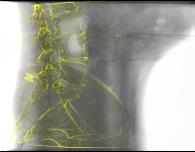

Deep Learning-based 2D/3D registration methods are highly robust but often lack the necessary registration accuracy for clinical application. A refinement step using the classical optimization-based 2D/3D registration method applied in combination with Deep Learning-based techniques can provide the required accuracy. However, it also increases the runtime. In this work, we propose a novel Deep Learning driven 2D/3D registration framework that can be used end-to-end for iterative registration tasks without relying on any further refinement step. We accomplish this by learning the update step of the 2D/3D registration framework using Point-to-Plane Correspondences. The update step is learned using iterative residual refinement-based optical flow estimation, in combination with the Point-to-Plane correspondence solver embedded as a known operator. Our proposed method achieves an average runtime of around 8s, a mean re-projection distance error of 0.60 $\pm$ 0.40 mm with a success ratio of 97 percent and a capture range of 60 mm. The combination of high registration accuracy, high robustness, and fast runtime makes our solution ideal for clinical applications.